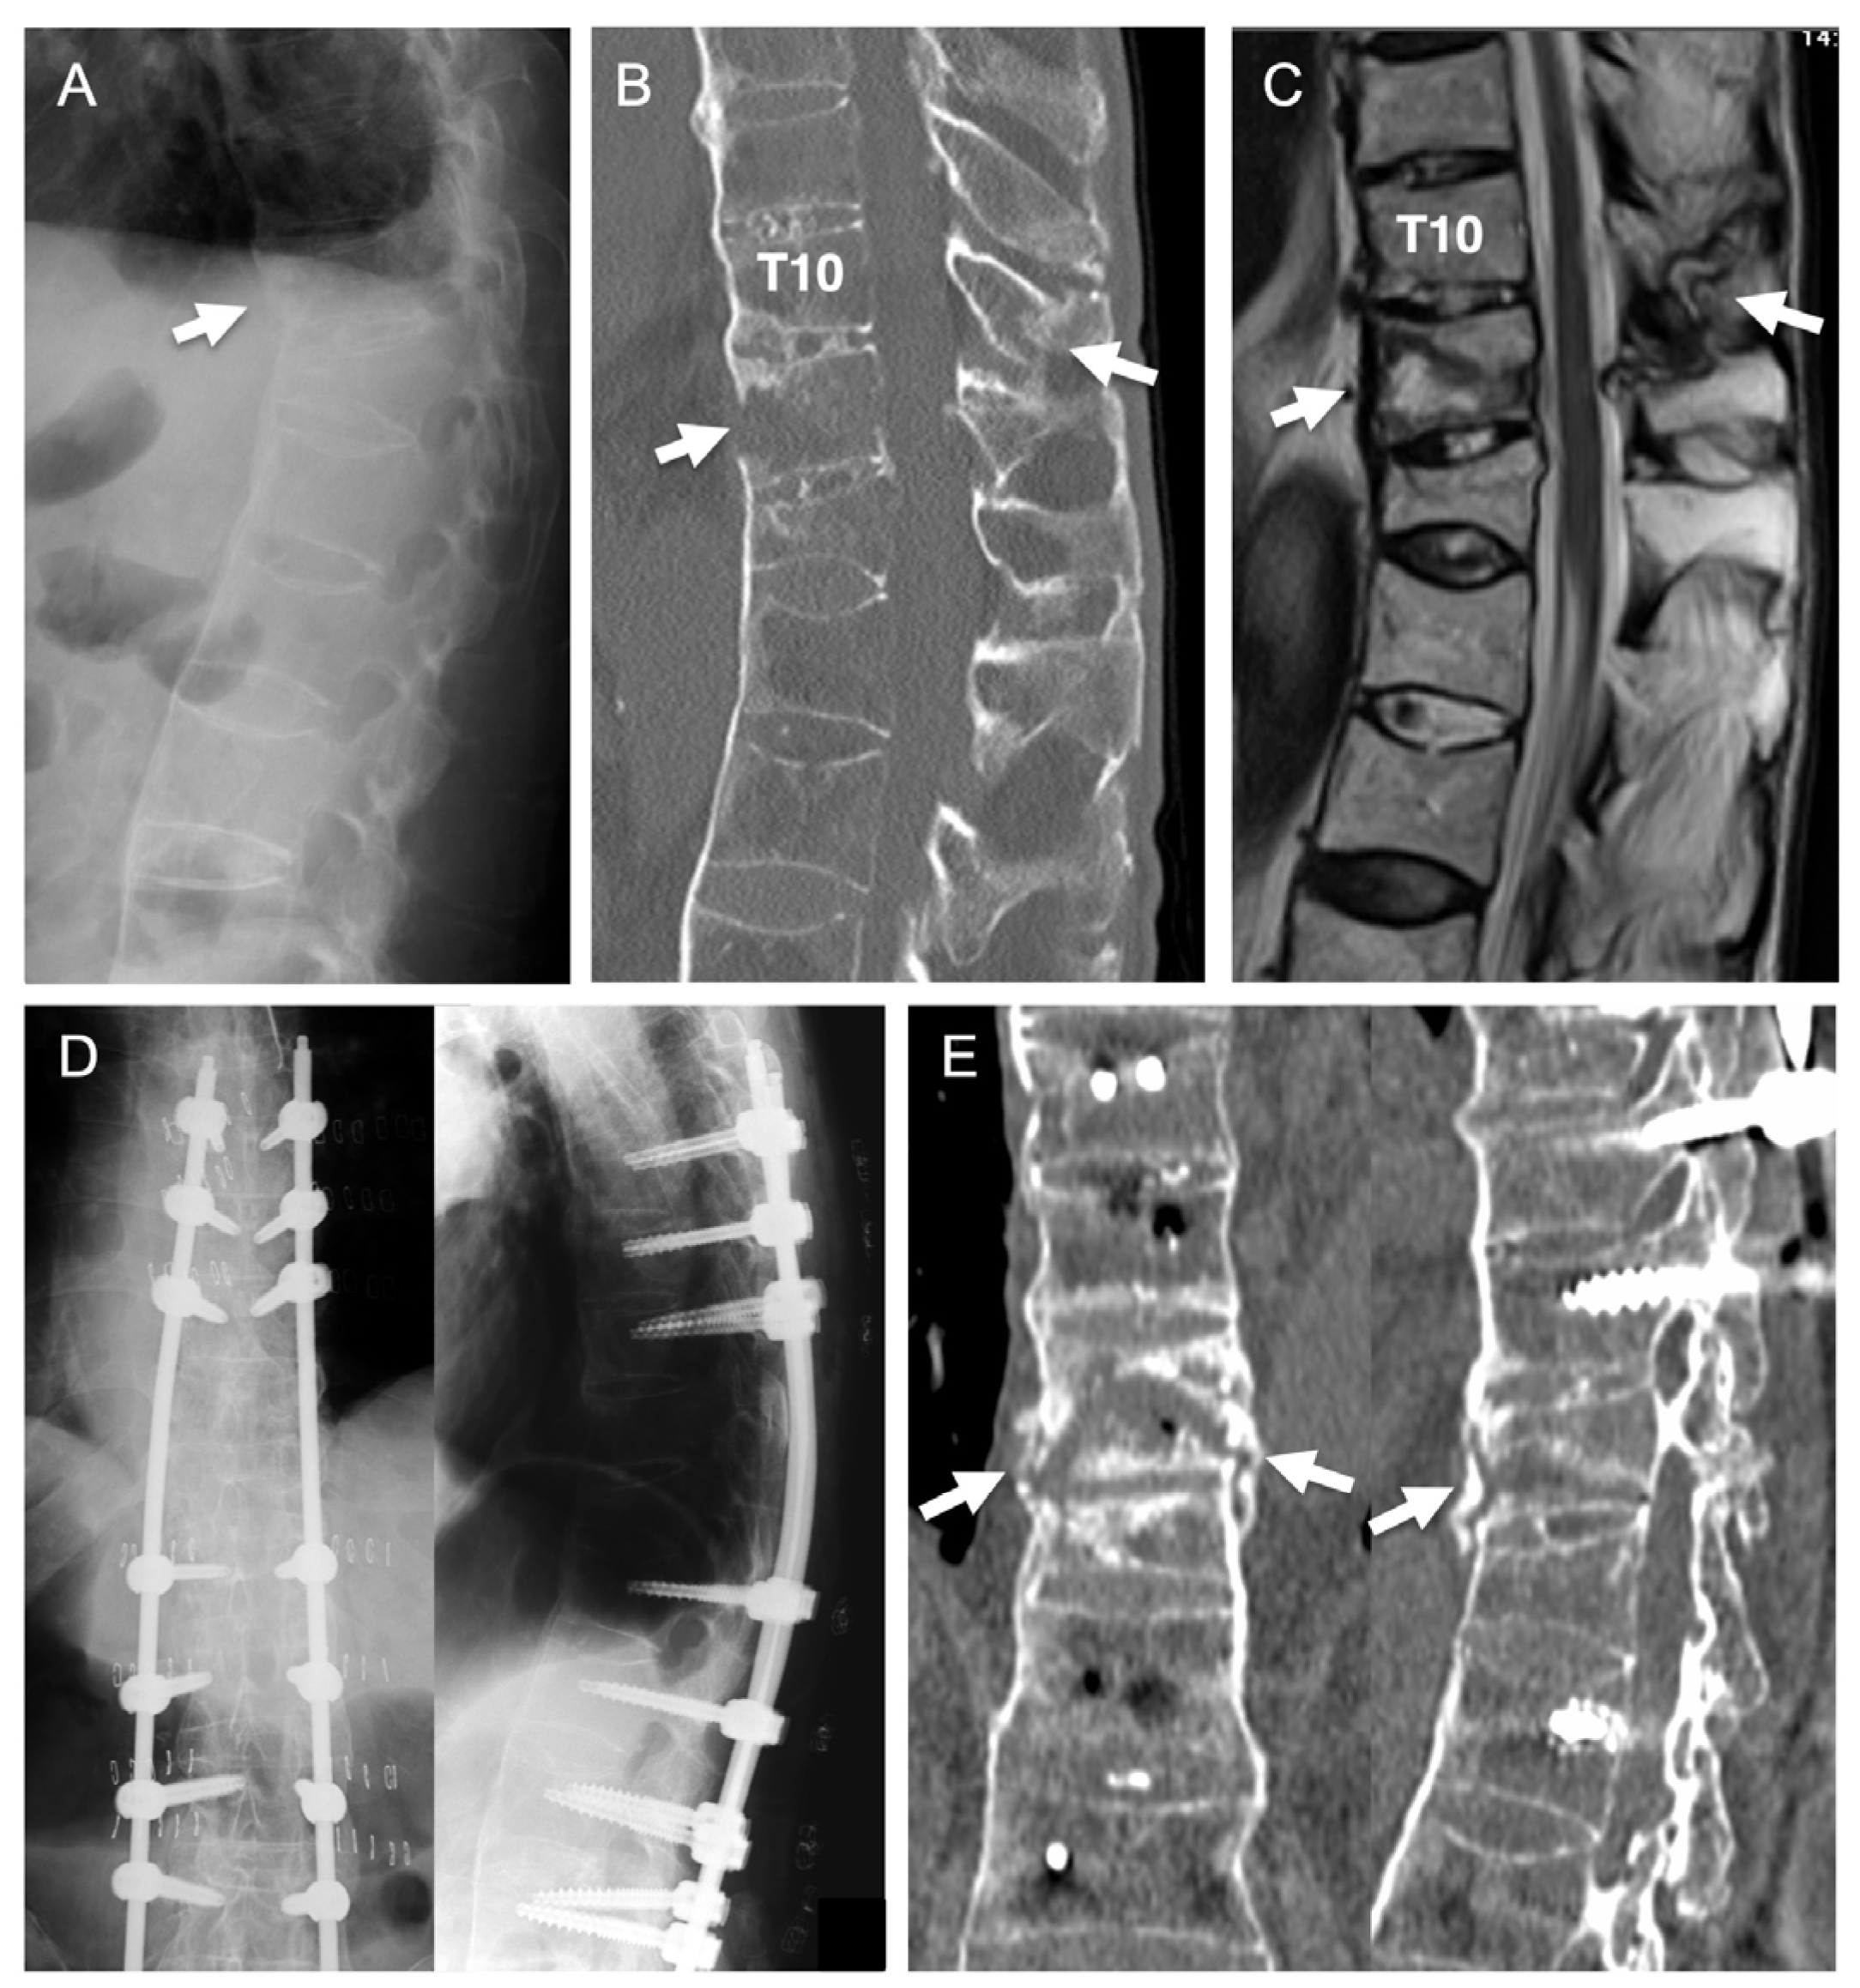

4. Postoperative Stability of PPS Fixation in Osteoporotic Patients

5. Illustrative Case